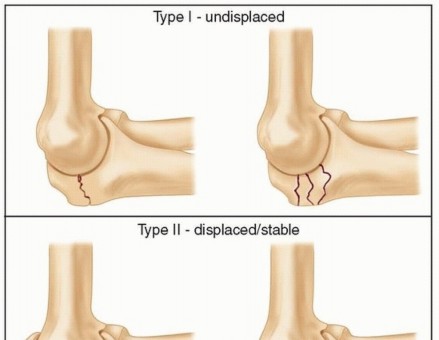

Jupiter and Ring Classification

Understanding the anatomical extent of the synostosis is critical for surgical planning. Jupiter and Ring classified proximal radioulnar synostosis into three distinct types based on anatomical location:

* Type A: Synostosis located at or distal to the bicipital tuberosity.

* Type B: Synostosis involving the radial head and the proximal radioulnar joint directly.

* Type C: Synostosis contiguous with bone extending across the elbow joint to the distal aspect of the humerus (extra-articular ankylosis).